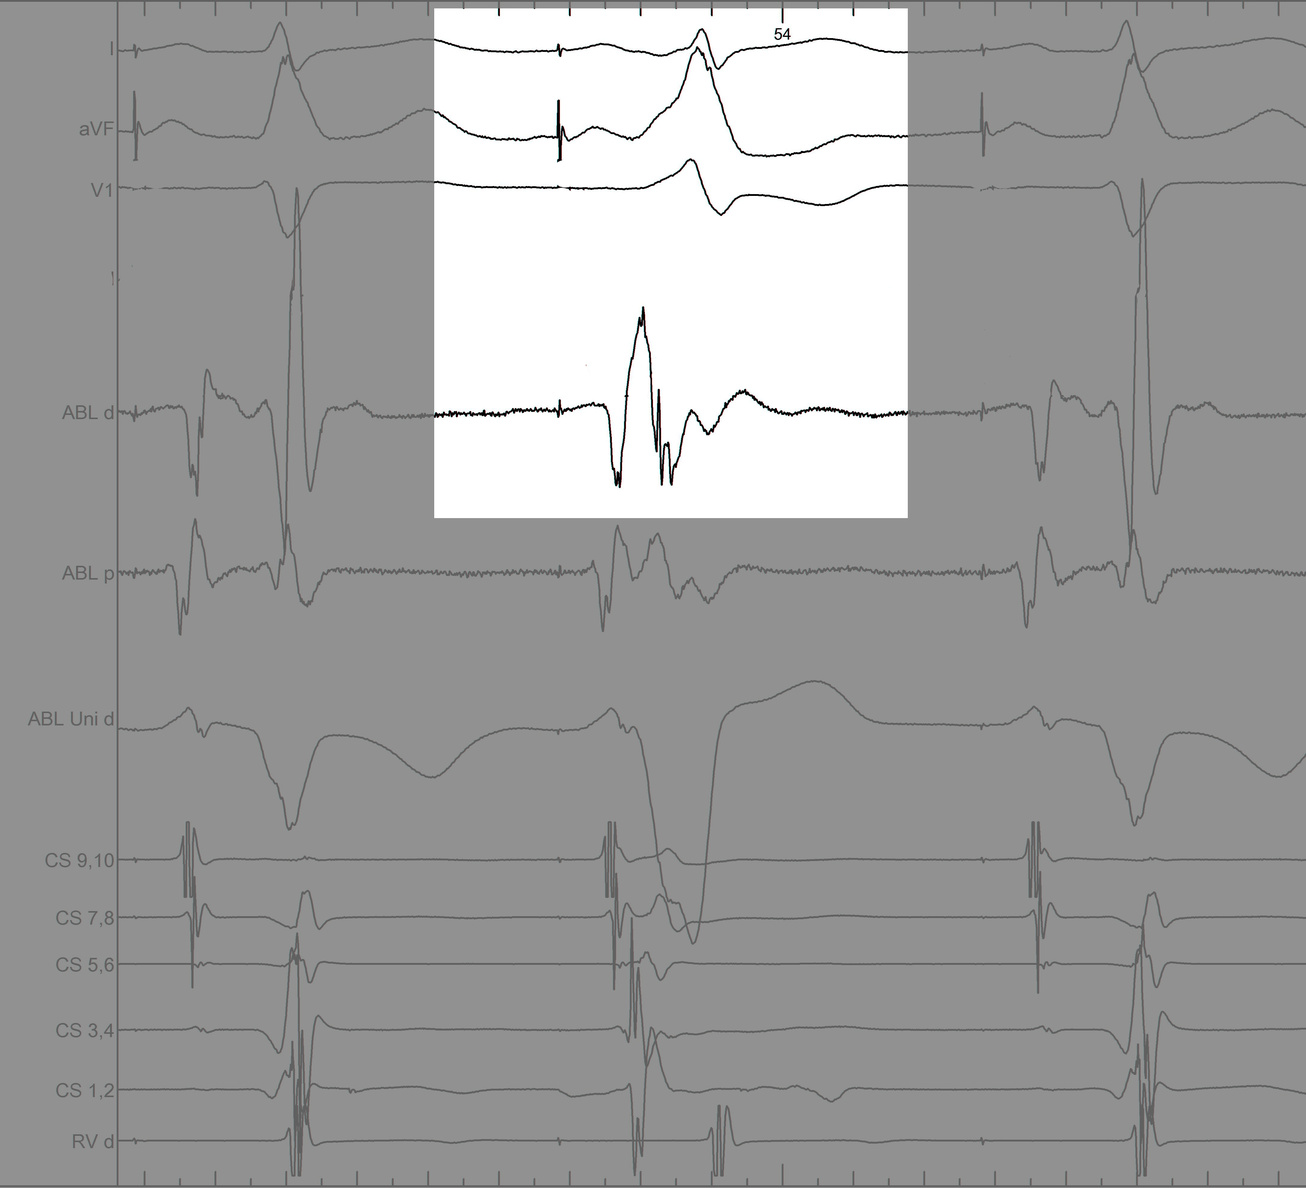

Identify components of the signal

mask1.jpg

mask2.jpg

mask3.jpg

mask4.jpg